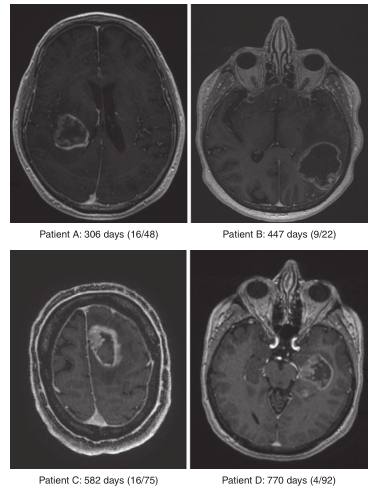

一般而言,电离辐射可促进免疫刺激事件,如(1)增加HLA分子表达,MHC-I表达,(2)产生与细胞毒性T细胞识别有关的特异性多肽,(3)通过释放肿瘤相关抗原促进细胞毒性T细胞活性。后一种过程导致效应细胞的激活和运输,促进原位细胞免疫反应,尽管也可能发生远距离反应。在这个特殊的背景下,剂量和分级似乎在诱导抗肿瘤免疫效应方面起着决定性的作用。Demaria组在乳腺癌和结肠癌模型上的临床前研究显示,除CTLA-4阻断外,联合局部分割放疗方案(8gy×3,6gy×5)有明显的抗肿瘤T细胞反应的迹象,其他临床前/临床研究能够支持这种联合方法的相关性。考虑到单克隆抗体对CTLA-4和PD-1调节的免疫抑制作用在转移性非小细胞肺癌、黑色素瘤和肾癌中的抑制作用,进一步研究辐射对局部和远处的潜在辅助作用是必要的。Postow等人报道了一例被诊断为转移性黑色素瘤的患者,用伊匹单抗治疗;在一个阶段,患者接受了低分割放射治疗,以治疗椎旁转移;患者接受了28.5Gy的治疗,分3次进行,为期7天。4到5个月后,椎管旁肿块和一组先前发现的远处肺门淋巴结病变和脾脏病变(不是放射靶点)明显减少。治疗10个月后CT仍显示病情稳定。在更大的患者群体中再现这些效应需要考虑许多生物学和临床变量,其中包括能够提供关于辐射诱导的免疫反应的定性和定量预测数据的数学模型。甚至可以反映“突变负荷”和T细胞浸润的图像分析也可能提供一种预测工具,同时也是一种用来衡量针对突变抗原的T细胞反应应该如何“集中”和缩小或扩大的工具(见Fig 4.3),以便提供更高的存活率。

Fig 4.3 对4例胶质瘤患者(WHO分级为4级)进行MRI扫描,以(I)术后数天的存活时间和(Ii)患者TIL所识别的突变表位数(由IFN-γ产生所确定的突变表位数与所识别的突变总数之比)为指标。集中的TIL应答似乎与提高存活率有关,这一观察结果需要在更大规模的研究中进行随访。

尽管数据表明非常集中的免疫识别在临床上更有利(根据存活率定义),但需要进行更多的基础和临床研究,以可视化突变负荷、识别的靶点数量、定制T细胞移植物靶向突变的可能性以及随后的临床反应性之间的联系。因此,在放疗和免疫检查点阻断联合治疗后,患者体内新表位特异性T细胞的激活是改善临床结果的关键,因此值得在有着良好控制的临床环境中进一步探索。对新抗原反应性T细胞表面组织归巢标记和记忆标记的全面分析,这些分析的结果与患者转移的解剖位置之间的关系,以及与T细胞的功能的关系对于丰富我们对癌症靶向细胞免疫治疗的理解是至关重要的。从接受治疗的患者身上获得的临床样本可以进行这些免疫学分析,即在“标准”或免疫治疗策略期间的不同时间点抽取的外周血液。进一步优化靶向T细胞治疗的另一个主要难题是缺乏对抗原处理和提呈的理解,即哪些表位是自然提呈的,它们各自的组织表达模式是什么,它们相应的HLA限制以及它们驱动抗原特异性T细胞反应的能力,基于能够对单个突变的靶表位发生反应的TCR谱系。对抗原特异性T细胞群体的“免疫学适应性”的进一步研究可能会影响基于细胞的治疗的效果,并进一步帮助定制T细胞产品。例如,T细胞治疗癌症、病毒感染和自身免疫性疾病的最新进展突出了工程T细胞的广泛治疗潜力。尽管人类原代T细胞的位点特异性遗传操作仍然具有挑战性,但它们在定制T细胞产品方面有着巨大的临床前景,例如,使用CRISPR和TALEN方法对T细胞进行基因组编辑,以及对T细胞不对称分裂进行详细分析,以便更好地理解和定义突变表位的质量,从而更好地产生即时免疫效应细胞和长期记忆T细胞。有关暴露于病原体和“环境因素”如何影响TCR谱系和最终疾病易感性的新的临床相关见解将有助于破译癌症患者针对突变表位的适应性细胞免疫反应中的分子“决策过程”,并提供必要的工具来加强治疗决策,为恶性肿瘤患者提供更有效、多层次和长期的细胞免疫反应。